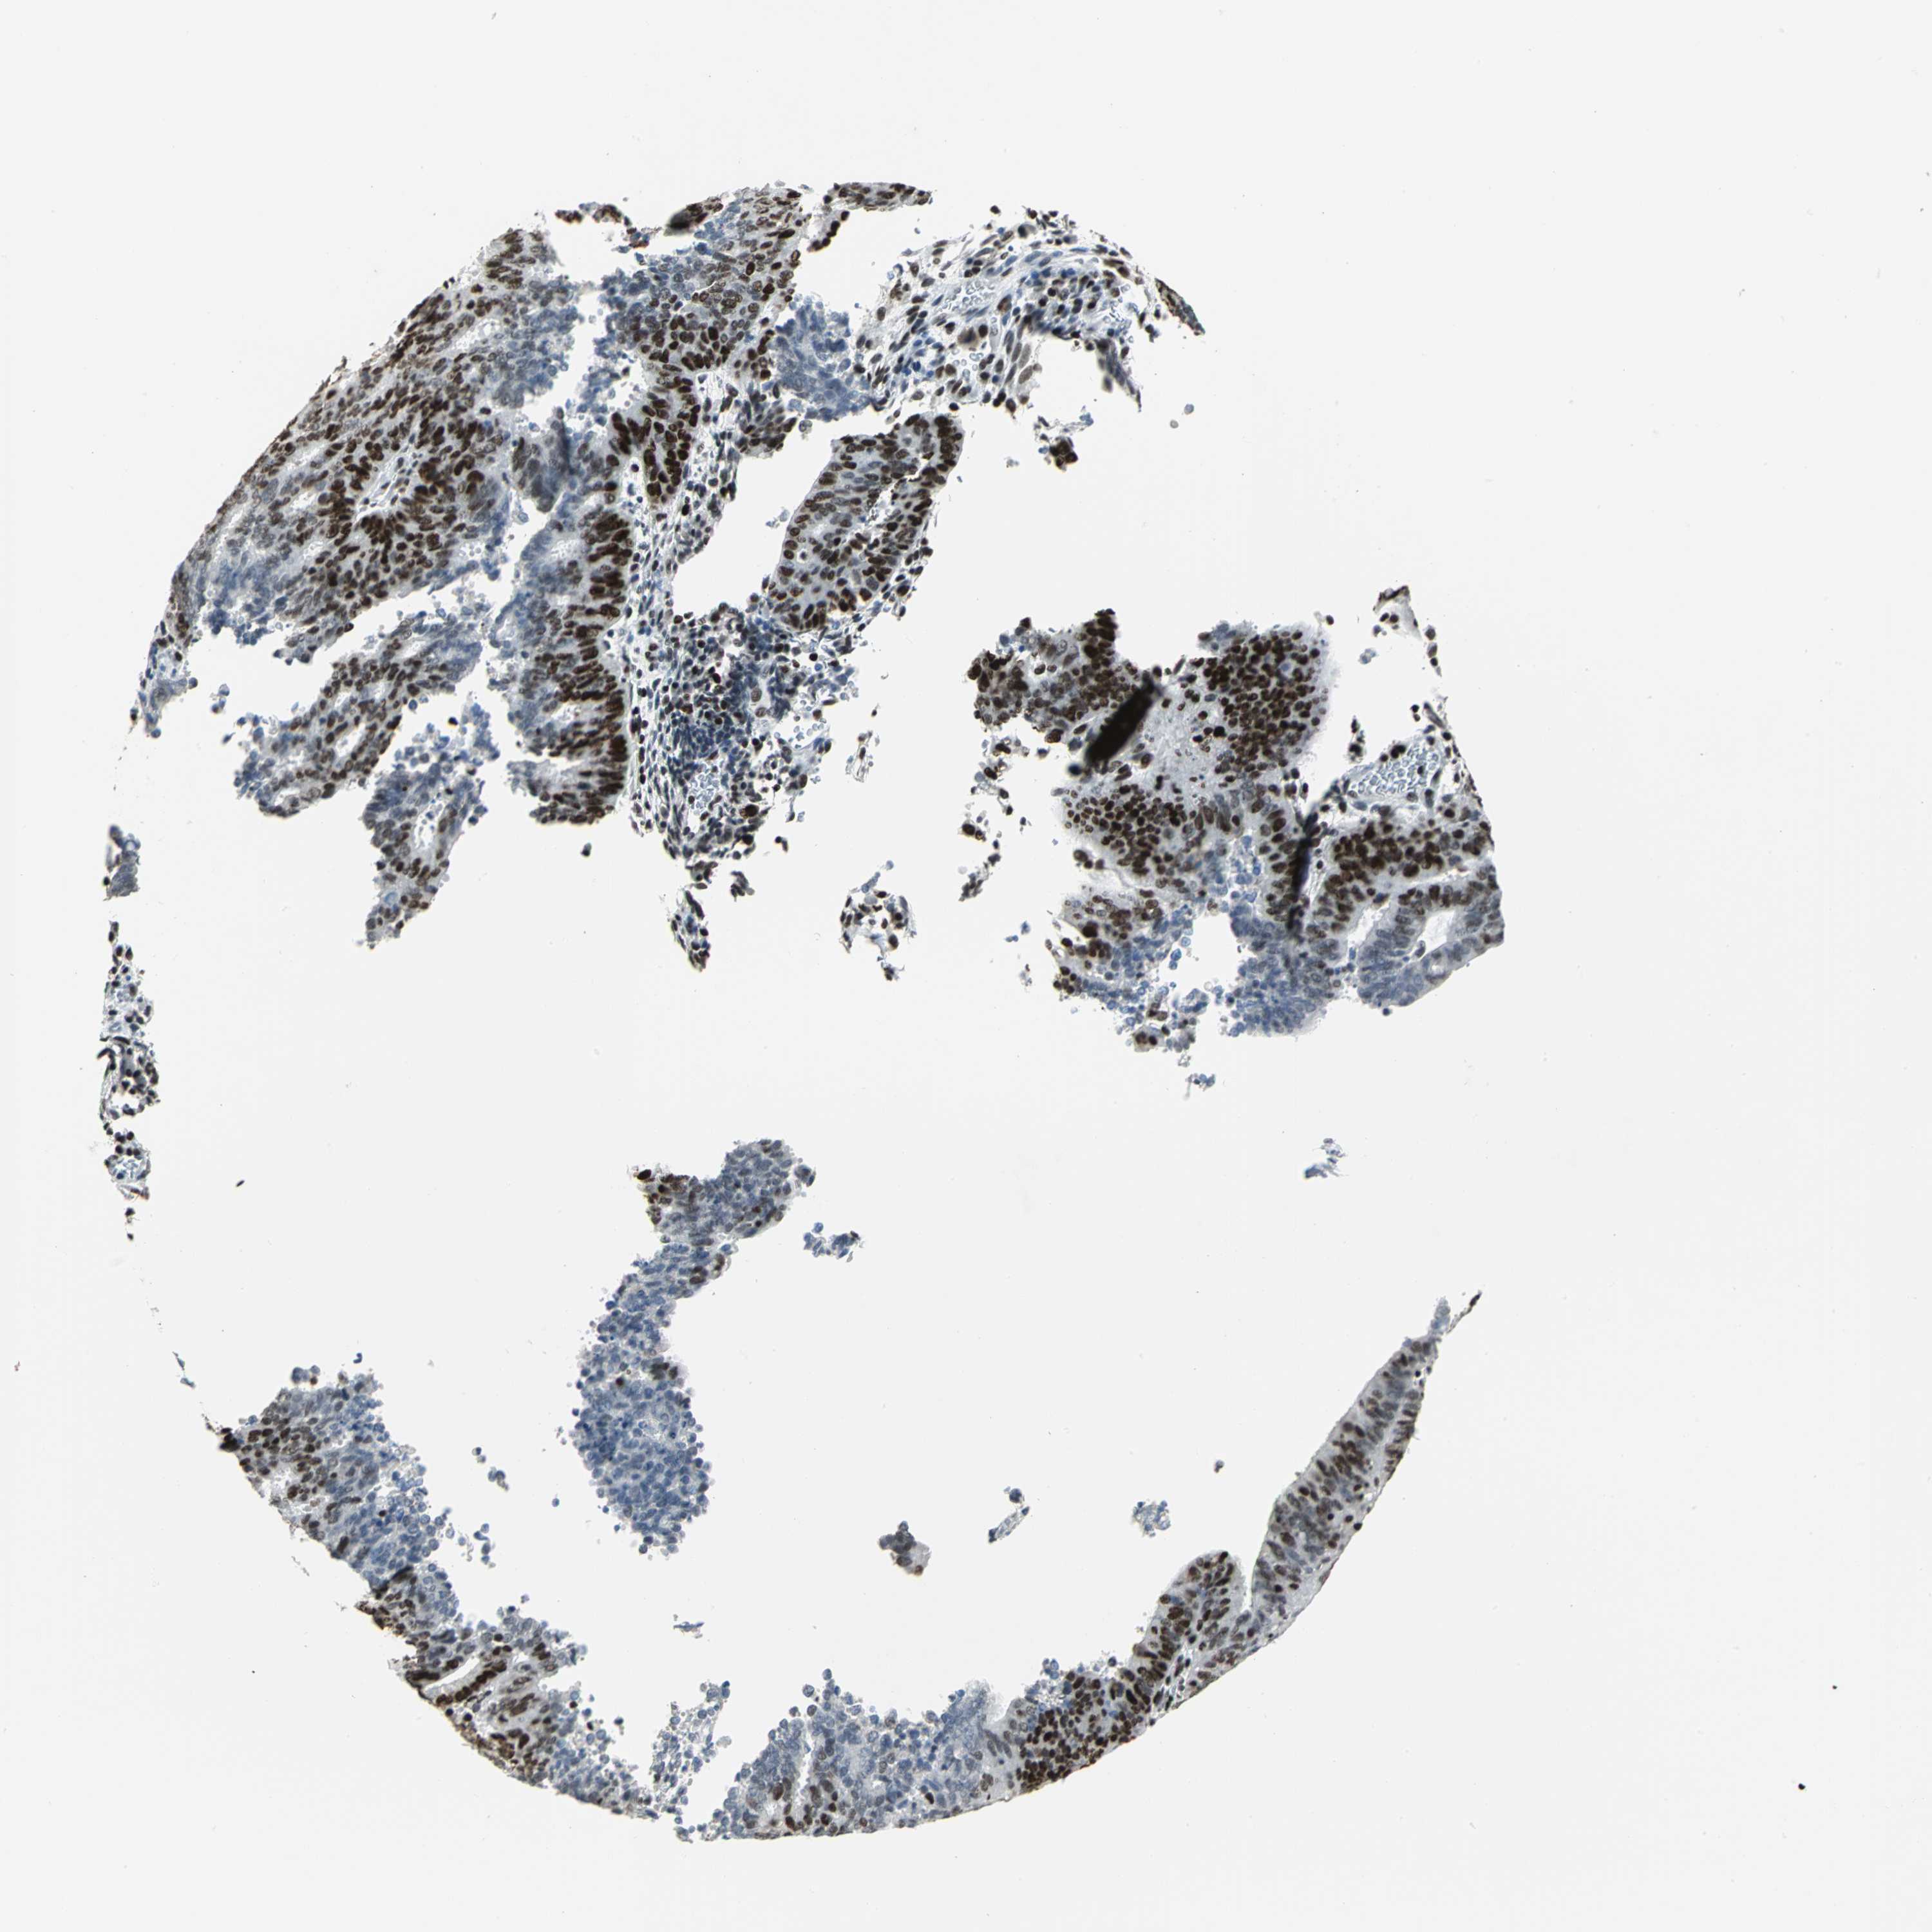

CERVICAL CANCER - Protein expressioni

A mouse-over function shows sample information and annotation data. Click on an image to view it in a full screen mode. Samples can be filtered based on level of antibody staining by selecting one or several of the following categories: high, medium, low and not detected. The assay and annotation is described here.

Note that samples used for immunohistochemistry by the Human Protein Atlas do not correspond to samples in the TCGA dataset.

Antibody stainingi

Antibody staining in the annotated cell types in the current human tissue is reported as not detected, low, medium, or high, based on conventional immunohistochemistry profiling in selected tissues. This score is based on the combination of the staining intensity and fraction of stained cells.

Each image is clickable and will lead to virtual microscopy that enables deeper exploration of all samples and also displays staining intensity scores, fraction scores and subcellular localization as well as patient and tissue information for each sample.

Antibody HPA004911

Staining

High

Medium

Low

Not detected

Intensity

Strong

Moderate

Weak

Negative

Quantity

>75%

75%-25%

<25%

None

Location

Nuclear

Cytoplasmic/membranous

Cytoplasmic/membranous,nuclear

Squamous cell carcinoma, NOS

Adenocarcinoma, NOS